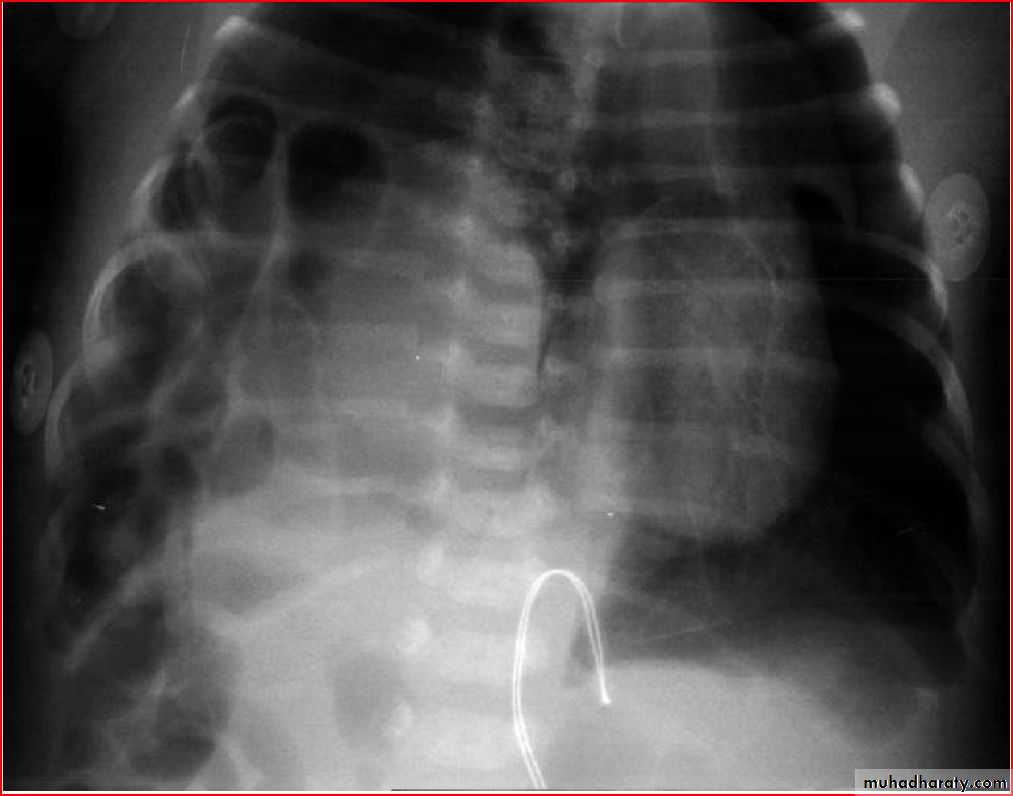

Enlarged hilar lymph nodes + non hemogenous opacity of middle and lower lobe

TBPleural effusion meniscal sign